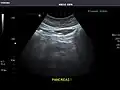

Abdominal Ultrasound (Full Exam)

STRUCTURED REPORT

(Technique: Transabdominal ultrasonography; Device: Toshiba Aplio XG)

Liver: Diffusely homogeneous and normal in echogenicity. No focal mass or contour nodularity. No intrahepatic biliary ductal dilatation.

Portal Vein: Patent main portal vein.

Gallbladder: No stones, wall thickening, or pericholecystic fluid.

Common Bile Duct: Nondilated measuring 1.3 mm at the level of the porta hepatis.

Pancreas: Visualized portions unremarkable.

Spleen: Normal in size.

Kidneys: Right and left kidneys measure 11.5 cm and 12 cm in length respectively. No hydronephrosis. Small left lower pole kidney cyst.

Ascites: None.

Aorta: Visualized portions normal in caliber, 16 x 15 mm.

IVC: Normal.

IMPRESSION:

Normal abdominal ultrasound.